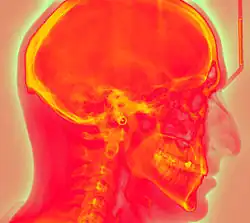

Photostimulated luminescence (PSL) is the release of stored energy within a phosphor by stimulation with visible light, to produce a luminescent signal. X-rays may induce such an energy storage. A plate based on this mechanism is called a photostimulable phosphor (PSP) plate (or imaging plate) and is one type of X-ray detector used in projectional radiography. Creating an image requires illuminating the plate twice: the first exposure, to the radiation of interest, "writes" the image, and a later, second illumination (typically by a visible-wavelength laser) "reads" the image. The device to read such a plate is known as a phosphorimager (occasionally spelled phosphoimager, perhaps reflecting its common application in molecular biology for detecting radiolabeled phosphorylated proteins and nucleic acids).

Projectional radiography using a photostimulable phosphor plate as an X-ray detector can be called "phosphor plate radiography"[1] or "computed radiography"[2] (not to be confused with computed tomography which uses computer processing to convert multiple projectional radiographies to a 3D image).

In phosphor plate radiography, the imaging plate is housed in a special cassette and placed under the body part or object to be examined and the x-ray exposure is made. The imaging plate is then run through a special laser scanner, or CR reader, that reads and converts the image to a digital radiograph. The digital image can then be viewed and enhanced using software that has functions very similar to other conventional digital image-processing software, such as contrast, brightness, filtration and zoom. CR imaging plates (IPs) can be retrofitted to existing exam rooms and used in multiple x-ray sites since IPs are processed through a CR reader (scanner) that can be shared between multiple exam rooms.[6]